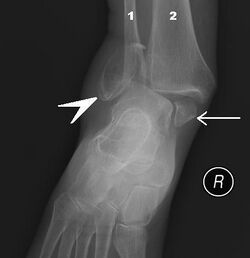

Рентгенограмма голеностопного сустава.

В ходе объективного обследования применяются физикальные методы исследования: осмотр, пальпация. Немаловажное значение имеет тщательный сбор анамнеза. Из инструментальных методов большое распространение получило рентгенологическое исследование голеностопного сустава в прямой, боковой, а также косой проекции. В настоящее время для диагностики применяют также артроскопию.